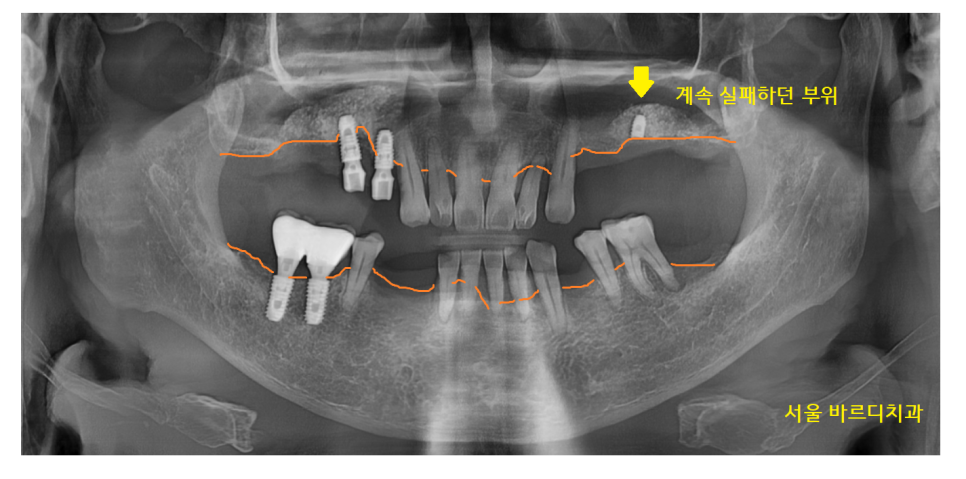

23년 2월 16일 환자분을 처음 만나게 되었습니다.

이전에 다른 치과에서 치료를 받으셨지만

계속 실패를 하셨다고 합니다.

전반적으로 잇몸 뼈가 많이 내려가신 상태

기존 치아 중에서도 문제가 많았습니다.

23.02.16

잇몸뼈가 녹아서

뽑아야 할 치아가 있었습니다.

다른 치과에서 심어놨던

임플란트도 제거가 필요했고요.

계속된 수술 실패로

많이 지쳐있으셨던 환자분

그동안 힘드셨던 부분을 잘 알고 있었기에

"내비게이션 임플란트" 치료를 권유 드렸는데요.